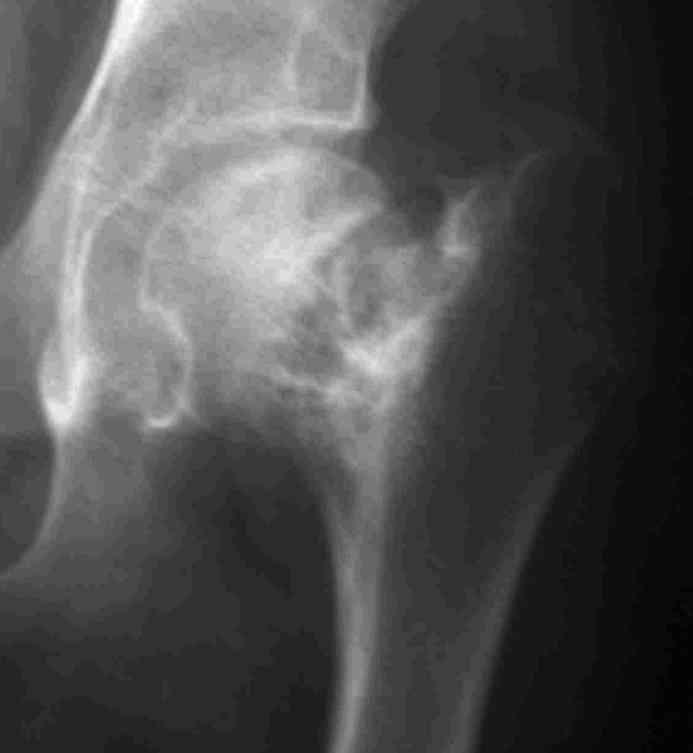

Интересует возможность одномоментного устранения очага ФД и корригирующей остеотомии, хотя я склоняюсь к двухэтапной тактике.Когда я впервые увидел этого подростка, сразу после снятия гипсовой повязки, консолидации не было и в планах была экскохлеация с медиализирующей вальгирующей остеотомией. Сейчас, когда консолидация отчетливая, возможно ограничимся только вальгизацией.На мой взляд надо оствить приемлемые условия для последующего ТЭП. Удивляет столь закрепившееся в практике мнение о возможности спонтанного восстановления костной после патологических переломов при кистах и ФД.

Около 16 лет наблюдаю пациента с ФИБРОЗНОЙ ДИСПЛАЗИЕЙ левой нижней конечности, полиосальная форма. Прилагаю рентгенснимки.